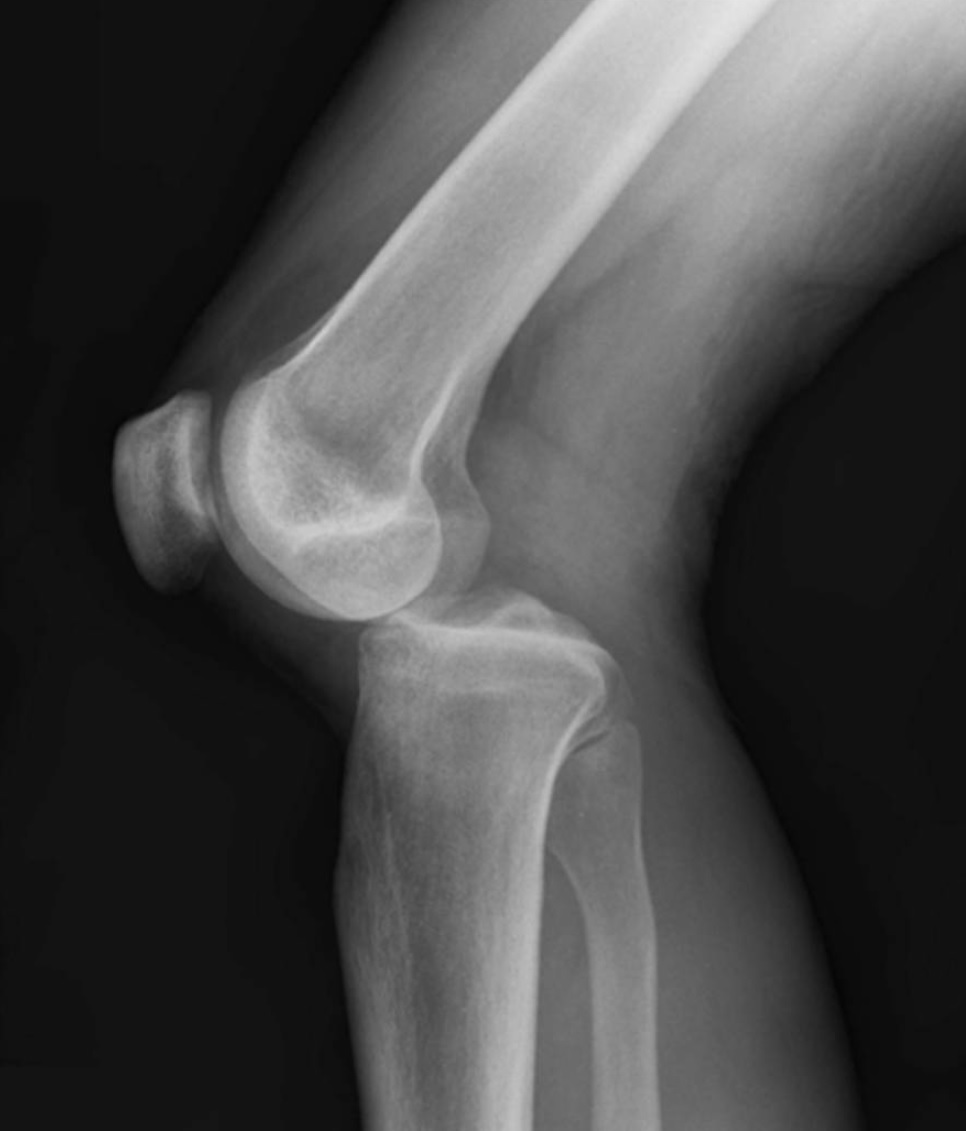

What is the MOI of patella dislocation?

A

1. External rotation of the tibia flexed

- ex. football players